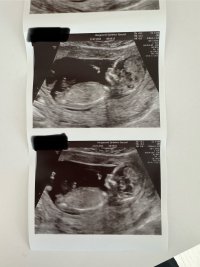

Her er vår lille krabat. Veldig aktiv og alt var helt perfekt❤️ Jordmor sa «denne er kommet for å bli», så det var gode nyheter. 12+2 i dag.

• C7F23BF7-41CC-4465-A78A-83EFD7DC60F7.jpeg

C7F23BF7-41CC-4465-A78A-83EFD7DC60F7.jpeg

222,6 KB · Visninger: 58